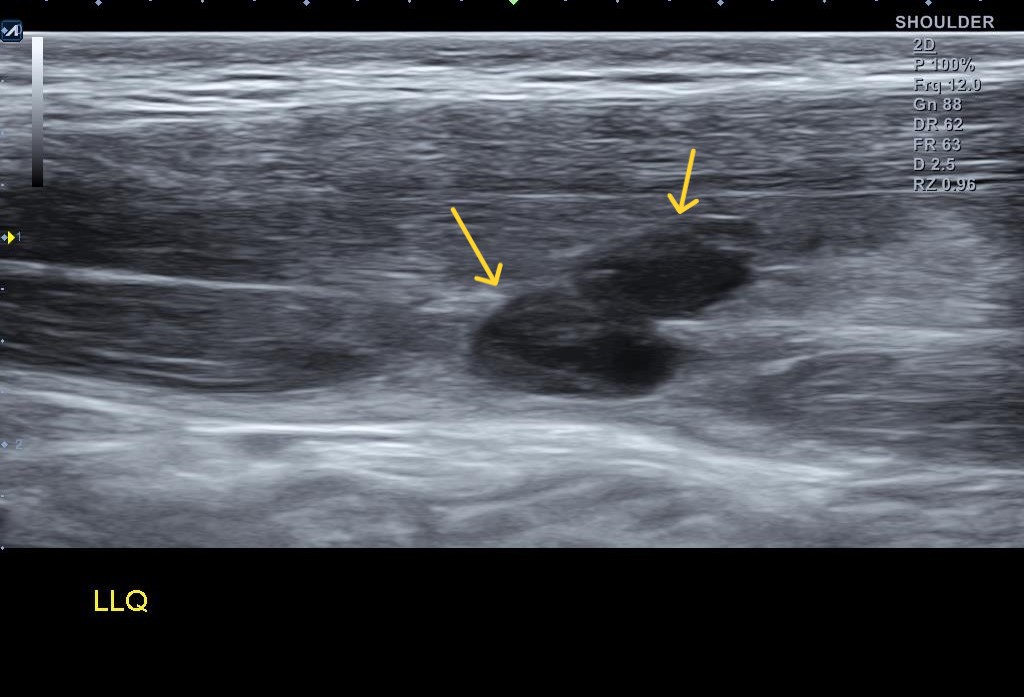

무조건 시합은 뛰어야 한다고 했던 환자.. 부상과 통증을 참고 어쩔 수 없이 시합에 참가한 후 부상이 심해진 걸로 보입니다. 좌측 하복부에 압통은 좀 더 심해져 있었고 주변에 멍까지 든걸로 봐서는 복직근 파열이 더 심해졌을 것으로 추측이 되었습니다.

왜 슬픈 예감은 틀린적이 없을까요...일주일만에 다시 시행한 초음파 검사 상에서는... 복직근 파열이 훨씬 심해져 있었습니다.

나 : 초음파 한번 보세요.... 지난주에 비해 파열 크기가 훨씬 커졌어요... 근육에 빵꾸가 2개나 나버렸어요...